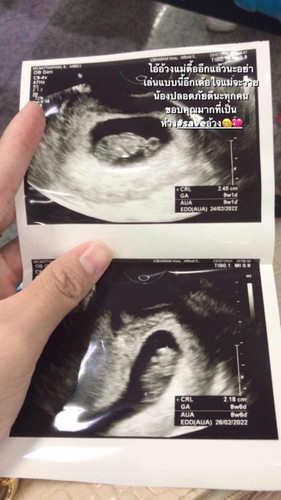

9week ท้องแรก💖

เกี่ยวมั้ยค่ะ?ท่องอ่อนห้ามเดินเยอะหรือมดลูกขยายตัวอะ พอดีว่าวันนี้มีเลือกออกจากช่องคลอดอีกแล้ว แต่โล่งอกแล้วหมอบอกว่าตัวเล็กแข็งแรงดี #ท้องแรก #9week 💖🥰#ขอบคุณล่วงหน้านะคะ #ขอบคุณสำหรับคำตอบค่ะ #ใครมีประสบการณ์